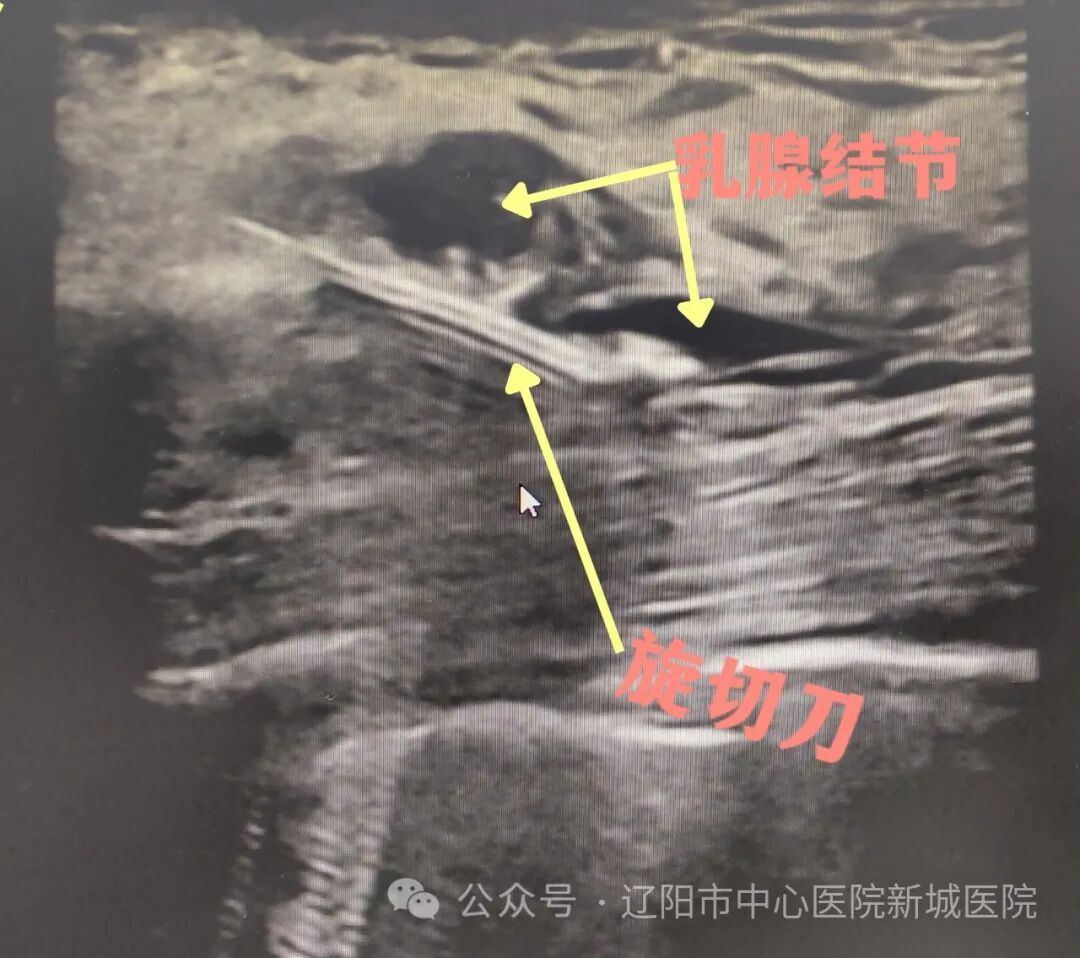

乳腺微創(chuàng)旋切術(shù)也叫真空輔助乳腺活組織檢查(VAB),通常在超聲引導(dǎo)下的局麻微創(chuàng)手術(shù),皮膚切口3-5mm。在超聲定位引導(dǎo)下,將旋切探針穿過(guò)皮膚,精準(zhǔn)到達(dá)目標(biāo)病灶下方;在負(fù)壓吸引下,將病灶組織吸入旋切刀的收集槽中進(jìn)行旋切后,由真空運(yùn)送系統(tǒng)運(yùn)出體外。重復(fù)上述旋切步驟,直至在彩超下看到病灶完全切除。

2.定位精準(zhǔn)。手術(shù)全程在彩超引導(dǎo)下操作,可準(zhǔn)確切除病灶,尤其是切除多發(fā)病灶優(yōu)勢(shì)明顯。